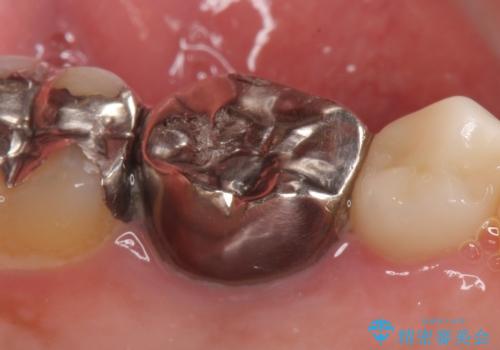

- 左下6番目の銀歯をオールセラミッククラウンにやり替えた症例です。

根管充填が不十分だったため再根管治療も行っております。